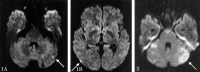

Results: DW images showed new hyperintense lesions in 18 patients (69%), with seven (27%) incurring neurologic deteriorations. All symptomatic patients fully recovered by discharge. Fourteen (78%) of 18 patients showed new lesions proximal to the treated aneurysm; that is, in the cerebellar hemispheres. In three cases treated with the balloon-assisted technique, new hyperintense lesions were seen.